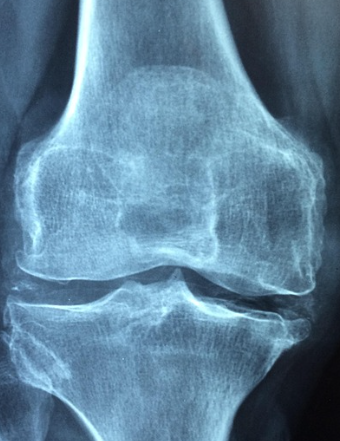

가장 잘 알려진 원인은 노화입니다. 나이가 들면 관절을 덮고 있는 연골이 점차 마모되고 손상됩니다. 연골은 충격을 흡수하는 완충 역할을 하는데, 이 기능이 약해지면 뼈와 뼈가 직접 맞닿아 통증과 염증을 유발합니다. 이로 인해 중·장년층에서 무릎, 고관절, 손가락 관절염이 흔히 발생합니다.

류머티즘 관절염은 대표적인 자가면역 질환으로, 우리 몸의 면역체계가 잘못 작동하여 자신의 관절을 공격하는 상태입니다. 활막(관절을 감싸는 막)에 염증이 생기며, 점차 뼈와 연골까지 손상시킵니다. 이 경우 원인은 외부 감염이나 노화가 아니라 면역계의 이상 반응에 있습니다.